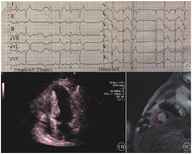

患者男,69岁,因"反复心悸伴胸闷4个月"来首都医科大学附属北京朝阳医院就诊。患者主诉4个月前出现心悸、憋气,24 h动态心电图提示频发室性早搏(室早),伴有同形态非持续性室性心动过速(室速)发作,室性心律失常负荷为28%。行心内膜导管消融失败,术后服用比索洛尔治疗。因药物治疗效果差,心电图仍提示室早频发。该患者20年前因活动后胸闷、胸痛,确诊冠心病并行冠状动脉旁路移植手术;11年前症状再发,诊断为心肌梗死(心梗),再次行经皮冠状动脉介入治疗;4个月前复查血管造影示血管通畅。患者另有高血压史40年、脑梗死后遗症、右眼失明(眼底动脉破裂);吸烟史20年,已戒烟。入院心电图(图1A)提示频发室早呈二联律,推测为左心室起源。入院彩色超声心动图示左心室射血分数(left ventricular ejection fraction,LVEF)保留(LVEF=64%),左心室舒张末期内径(left ventricular end-diastolic diameter,LVEDD)48 mm,但遗留左心室前壁及室间隔中间-心间部室壁瘤,局部室壁变薄,向外膨出(图1B)。术前行心脏延迟强化磁共振显像(delayed enhanced magnetic resonance image,DE-MRI),提示左心室室壁瘤形成,在左心室心尖部间隔部可见瘢痕延迟强化(图1C)。